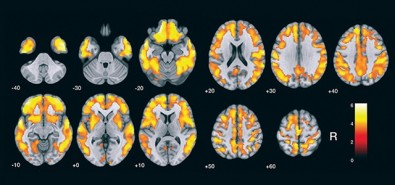

Depois de validar no Brasil a metodologia de detecção de placas amiloide no cérebro, os pesquisadores usaram um software para construir “mapas cerebrais estatísticos”. Os gráficos mostram a comparação das médias de 17 voluntários com suspeita de Alzheimer com as de outros 19 idosos saudáveis (grupo controle). Os resultados e a validação da metodologia foram descritos em artigo publicado na Revista Brasileira de Psiquiatria – RBP.

“Pelo mapa estatístico, é possível identificar facilmente o acúmulo de placas amiloides no grupo de pacientes com doença de Alzheimer, quando comparado ao grupo de voluntários saudáveis. As regiões do córtex estão claramente diferentes. Os mapas estatísticos são daquelas imagens que falam mais do que mil palavras”, disse Busatto.